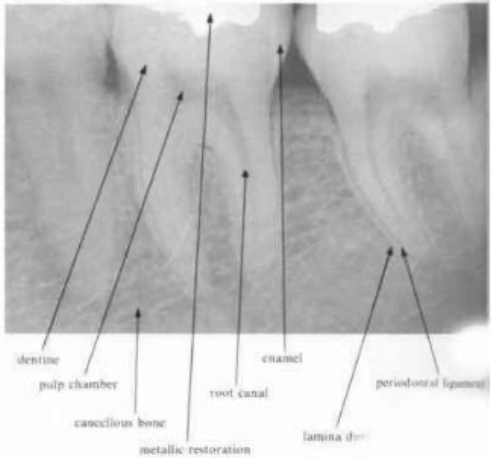

enamel & dentin

enamel → most radiopaque structure

dentin → should be uniform in density

cancellous bone

the bony trabeculae have a coarser pattern and run horizontally in MN

compare with the finer lace-like pattern in MX

periodontal ligament space

any definite widening in this area suggests the presence of pathology

should be narrow and even around the whole of the root surface that lies within the bone

lamina dura

is a radiographic artifact and it would be unwise to place to critical an interpretation on the variation in its appearance in diagnosis

despite the definite appearance of a white line surrounding the roots of teeth within bone, investigation has revealed that there is no increase in mineralization of the cancellous bone lining the tooth socket

pulp and pulp stones

pulp chamber & larger canals → readily visible on the radiograph

finer canals → those in the DB canal of the MX 1st molar may be more difficult to see

—root canals will never become completely sclerosed in the apical portion of the root